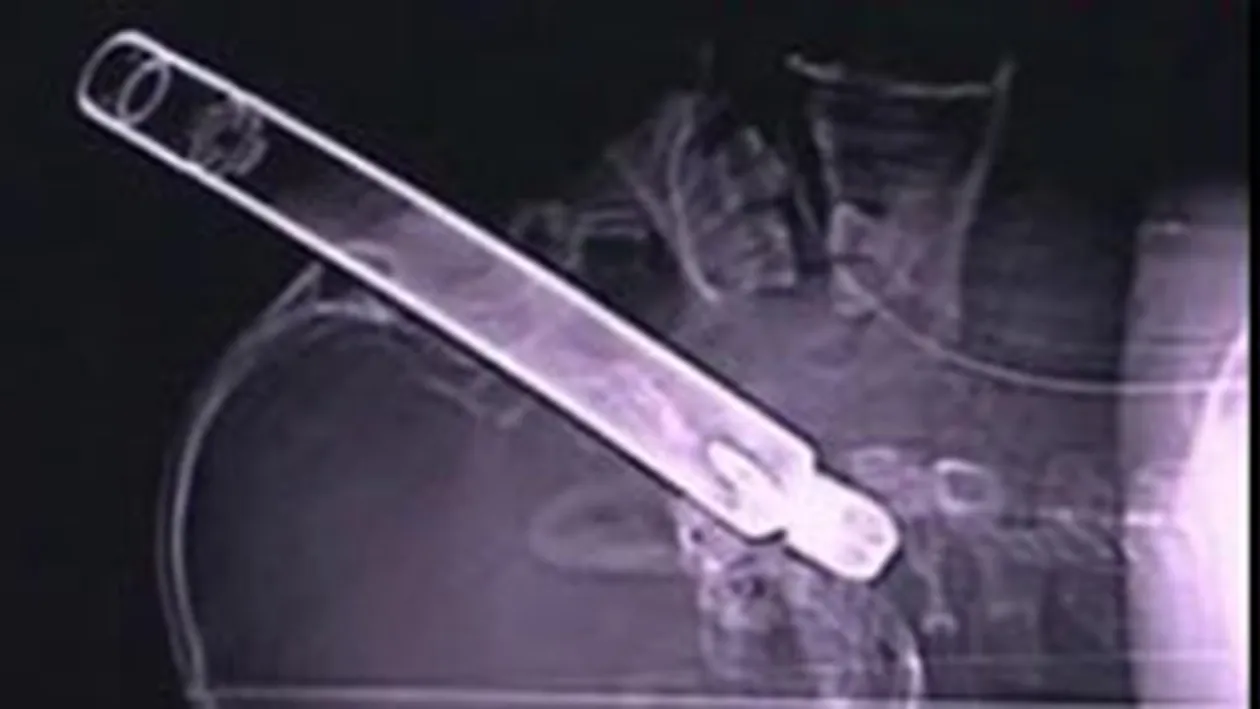

Un barbat de 43 de ani din Brasov a ajuns la spital cu o teava de metal de 30 de centimetri infipta in cap.

Acesta era mecanic auto si a reparat impreuna cu mai multi colegi un utilaj agricol. O piesa s-a desprins din masinarie si i s-a infipt in ochi.Barbatul a fost dus de urgenta la spital. In ciuda eforturilor medicilor, pacientul a decedat pe masa de operatie, din cauza unei hemoragii puternice.